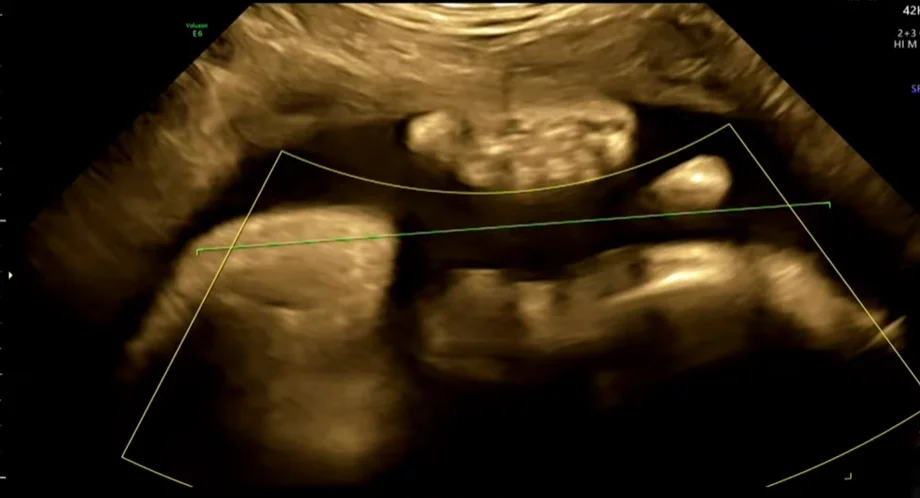

• Sinh trắc học thai nhi (Fetal Biometry)

• Thai chậm tăng trưởng trong tử cung (Fetal Growth Restriction - FGR)